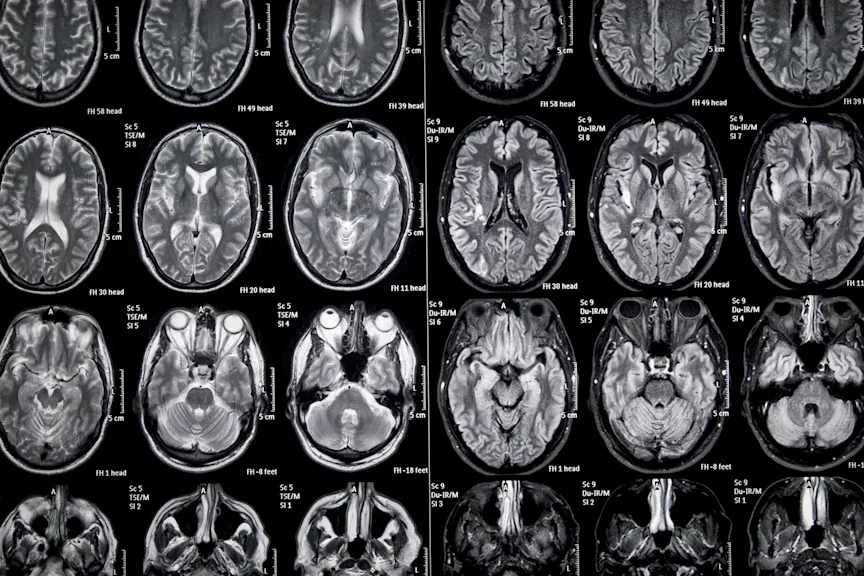

巴尔加瓦博士说,大脑损伤最初形成时,可以通过磁共振成像(MRI)扫描看到活动性炎症。他解释说,如果你的医生怀疑你有活跃的病变,你可能会做一个钆对比的核磁共振检查。钆是一种稀土金属,用来作为对比剂显示你身体最近的炎症区域。通常情况下,造影剂无法进入大脑或脊髓,这要归功于所谓的血脑屏障。但是当病变活跃时,他们会扰乱血脑屏障的正常防御。对比度泄漏到病变,它们在MRI上显然出现。

随着时间的推移,炎症消退,血脑屏障恢复正常,对比也不再显示在成像扫描上。巴尔加瓦博士说:“这样就会留下一个髓磷脂缺失的区域,我们称之为脱髓鞘。”你最终可能会在这些区域产生疤痕组织这些疤痕组织是由免疫细胞组成的小神经胶质细胞。

华博士说,病变比在临床上更频繁地展现出来(上述“沉默”病变。)。这就是为什么医生监控MS频繁MRI扫描,而不是等待患者呈现出症状。“我们希望看到沉默的疾病活动。我们想确保没有形成新病变,因为如果我们能够阻止病变形成,我们将大大降低残疾,“华博士说。

他解释说,通常每年都要做核磁共振。花医生说,如果你开始服用一种新药,你可能需要6个月的时间来确保药物发挥作用。一旦你长大了,炎症就会减缓。只要你的多发性硬化症稳定,你就不需要经常做核磁共振。

虽然MRI扫描是医生用来监测多发性硬化症的重要工具,但它们并不能提供全貌。“我们仍然依靠临床工具、其他测试和其他措施来真正帮助我们了解照顾病人的最佳方式,”华博士说。